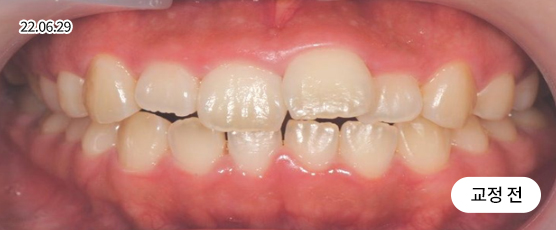

벌어진 치아교정 Solution

치아 벌어짐이 전체적으로 있는지 또는 부분(앞니 등)에만 있는지를 진단하고,

교정 장치를 부착하고 빈 공간으로 치아를 이동시켜 맞춰주는 방법으로 치료합니다.